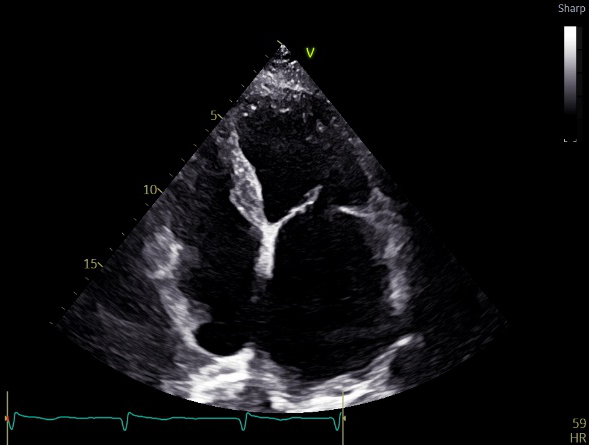

1月前感冒后再次出现胸闷、咳嗽症状,于当地医院查超声心动提示:“二尖瓣前叶脱垂,二尖瓣重度反流”,动态心电图提示:“心房颤动”,当地给予“呋塞米、螺内酯、诺欣妥、利伐沙班”等药物治疗,患者上述胸闷、咳嗽症状略减轻,但上楼2层以上仍存在胸闷、气短症状,为进一步诊治来我院,查超声心动提示:二尖瓣前叶对合点(A2、A3区)后移并重度反流,左心大(左室:44/60mm,左房:55*60*78),肺动脉高压(42mmHg),三尖瓣重度反流,右房大(54*71mm),现患者平素日常活动轻度受限,无夜间阵发性呼吸困难。

术前超声评估

术前超声诊断

LVOT-color:MR(重度),返流面积11.3cm2

肺静脉血流频谱呈收缩期反向

3D-color MV view:血流主要来源于2、3区

Qlab软件勾画估测瓣口面积约:6.16cm2